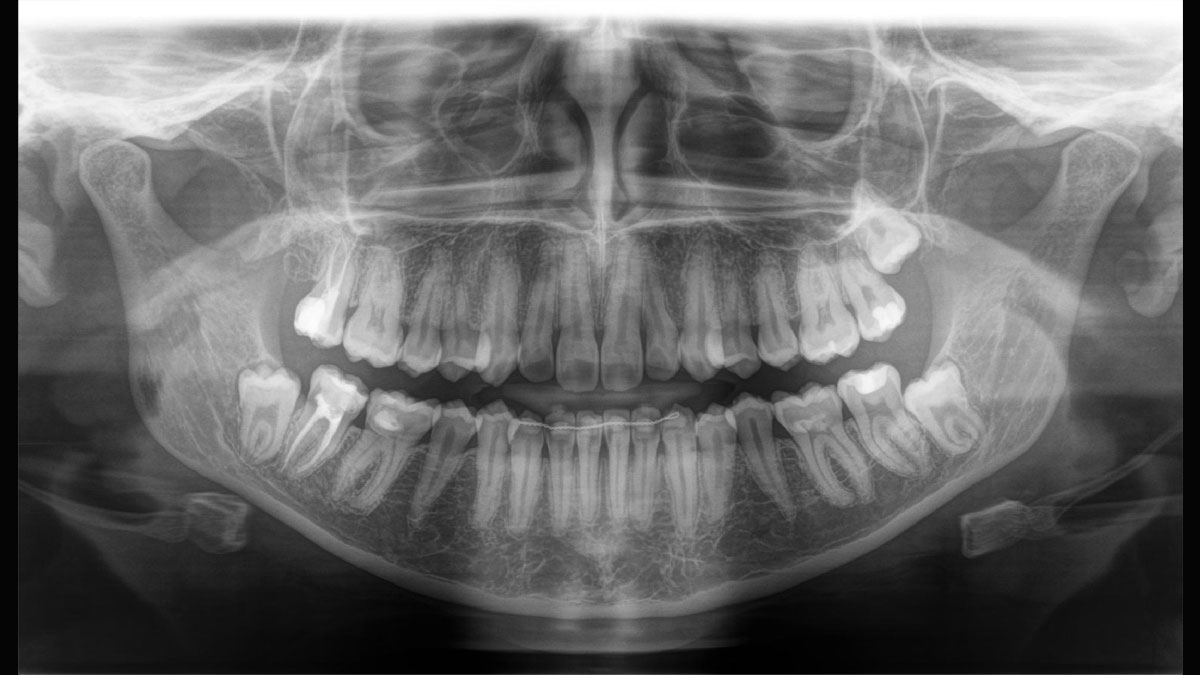

Der 2D/3D Power Performer Orthophos SL ist eine großartige Wahl für alle, die einfach mehr wollen. Der integrierte Direct Conversion Sensor (DCS) wurde für anspruchsvolle Bildqualitätsstandards entwickelt und bietet detaillierte Daten. Der intelligente Autofokus liefert automatisch fokussierte Panoramabilder mit hervorragender Gesamtschärfe. Orthophos SL bietet höchsten Bedienkomfort durch automatische Positionierung, eine anwenderfreundliche, intuitive Bedienung mit dem EasyPad und ein individuell einstellbares Umgebungslicht für ein exklusives Erscheinungsbild.

Der Direct Conversion Sensor erfüllt besonders hohe Standards für die 2D-Bildgebung

Der Autofokus erzeugt aus mehreren tausend Einzelbildern automatisch eine beeindruckende scharfe Panorama-Röntgenaufnahme

Der Direct Conversion Sensor (DCS) hat den Standard der Panorama-Bildgebung neu definiert. Röntgenstrahlen werden direkt in elektrische Signale umgewandelt – im Gegensatz zu herkömmlichen Systemen gibt es keinen Signalverlust durch Lichtumwandlung, was eine verbesserte Bildgebung ermöglicht. Das Ergebnis sind Bilder mit einer sehr hohen Schärfe, selbst bei niedriger Dosis.

Eine Röntgenaufnahme muss sofort diagnostizierbar sein. Der Autofokus hilft dabei erheblich. Orthophos SL erfasst mehrere tausend Einzelbilder in einem Zyklus und erkennt automatisch scharfe Bereiche, um ein gleichmäßig scharfes Gesamtbild zu erzeugen. Der intelligente Autofokus erfordert keine manuellen Arbeitsschritte vor und nach der Erfassung.